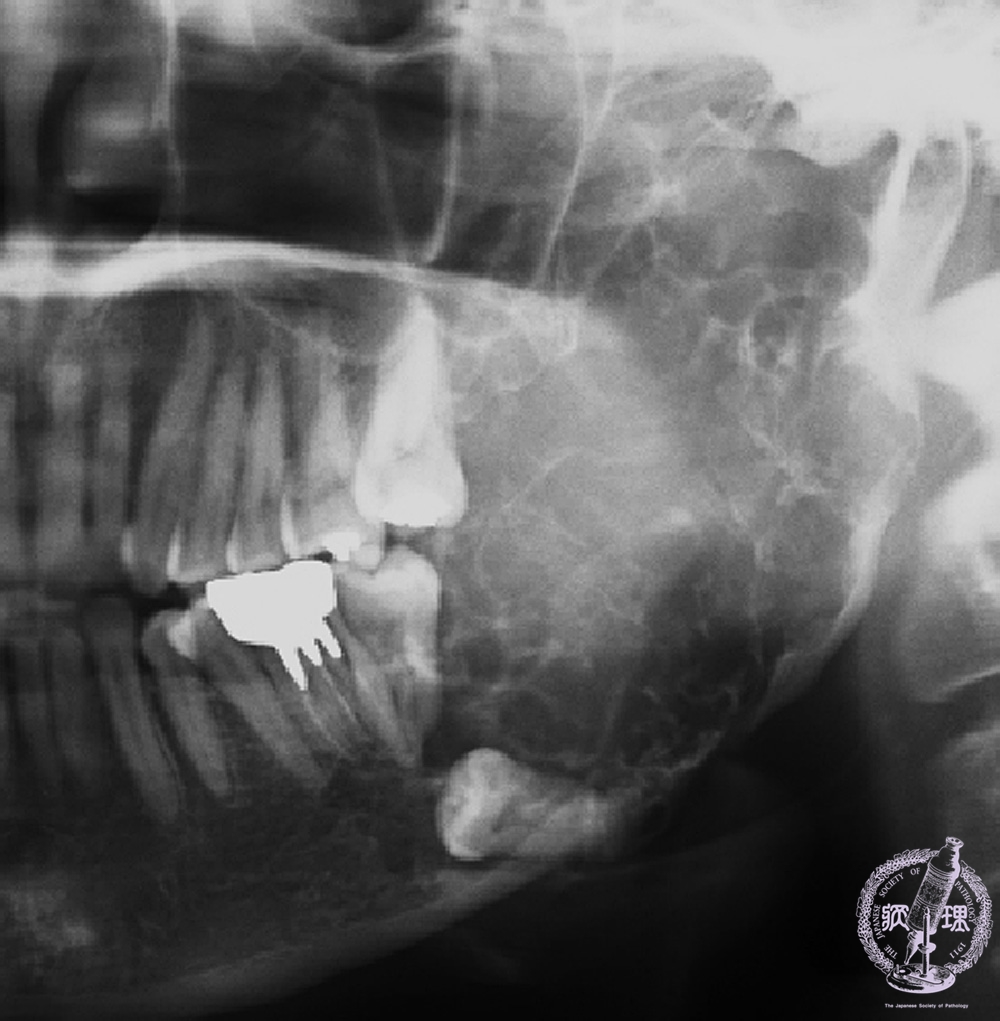

Panoramic radiograph:There is a multilocular, radiolucent and expansile bony lesion spanning from the left mandibular second molar to the coronoid and condylar processes. The third molar is impacted and the root of the second molar is resorbed (arrow).